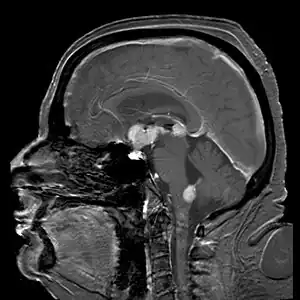

| Brain magnetic resonance imaging showing primary central nervous system B-cell non-Hodgkin lymphoma of the sella turcica and hypothalamus, continuing to the tectum (intensely white areas in the middle). | |